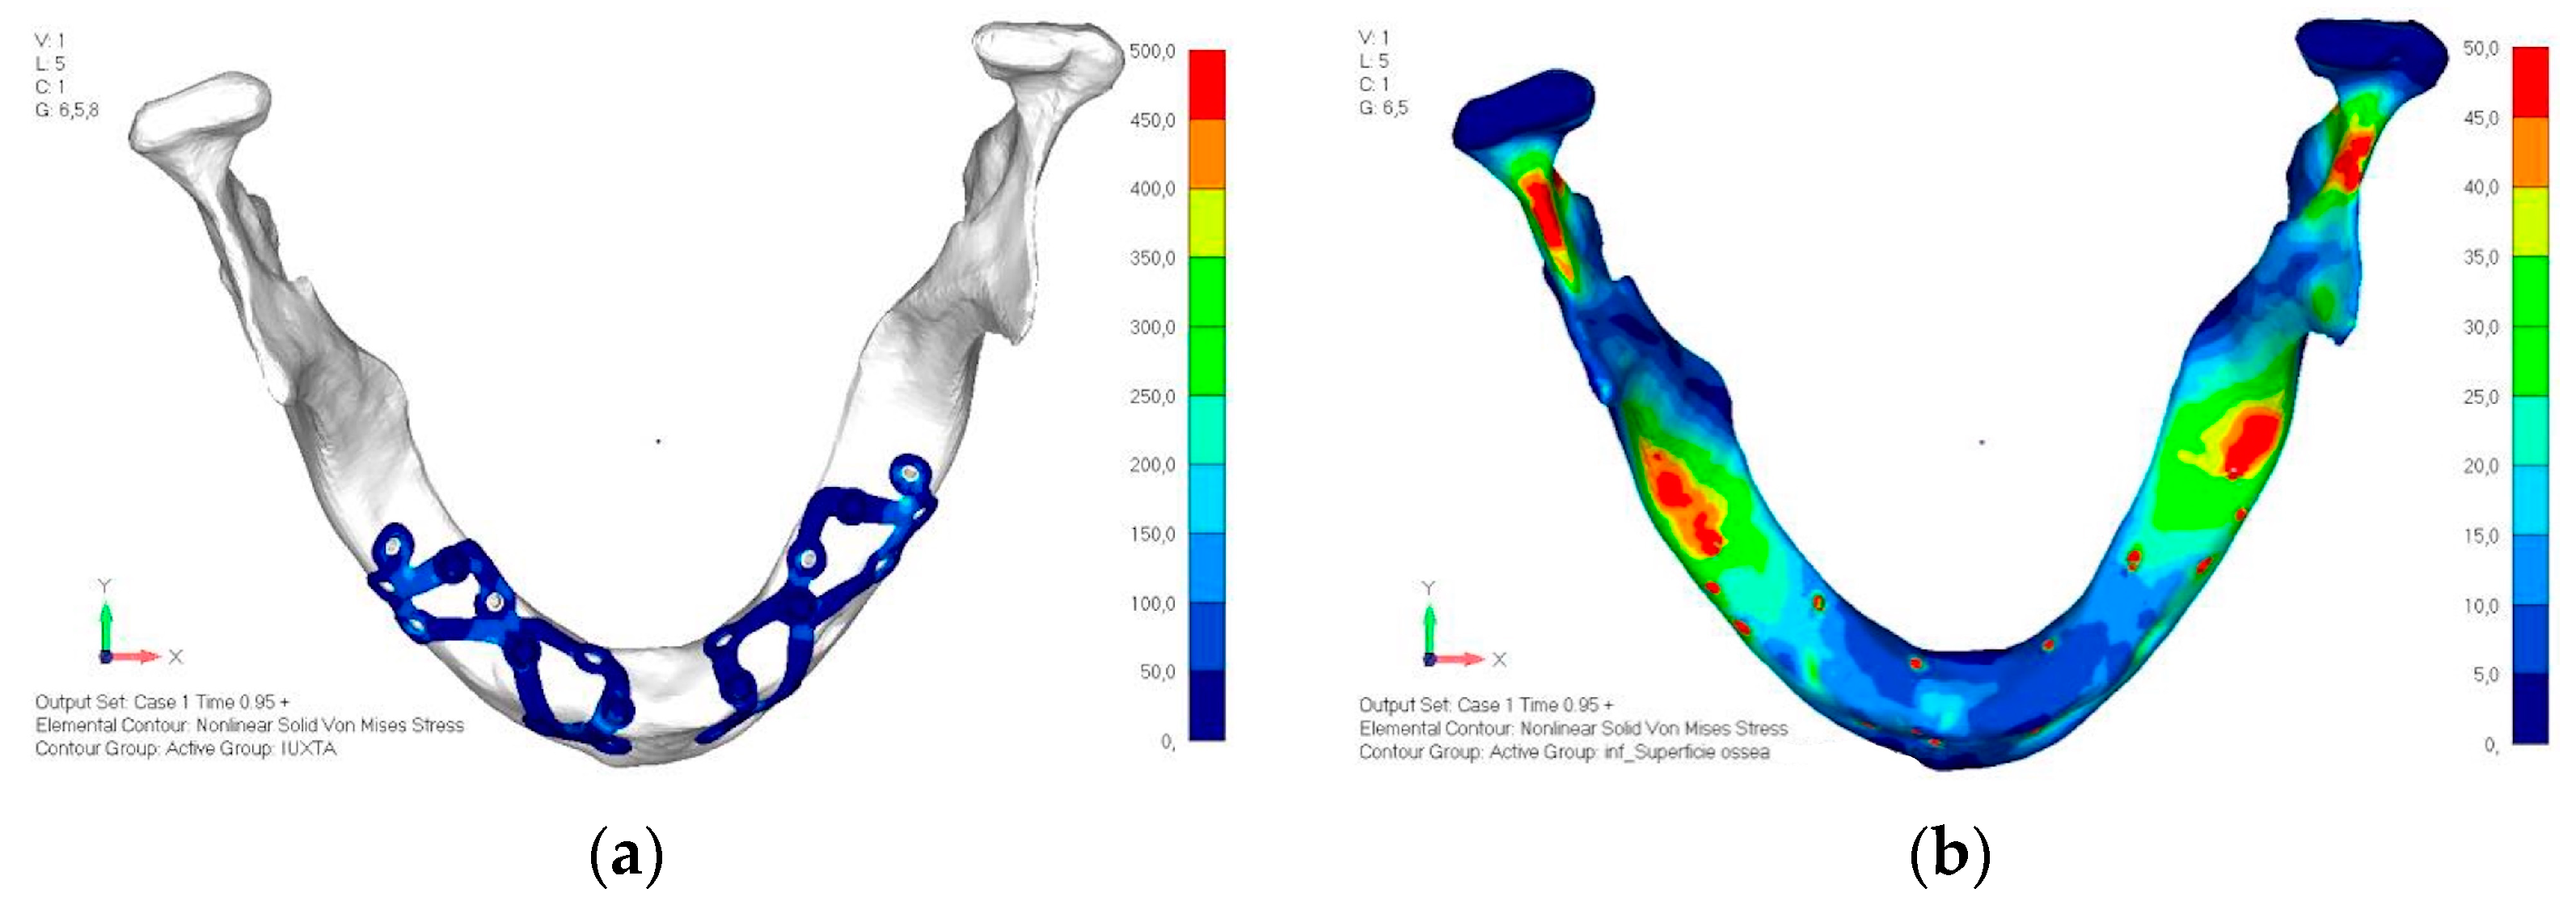

- Model V5. This version of the implant retains the same geometry as version 4, with the addition of two connecting bars, one on the lingual side and one on the vestibular side (Figure 31). The purpose of this analysis is to identify the differences between a monolithic implant and an implant divided into two hemi-arches. The results are quite similar to those observed in the upper model: the presence of a connection between the two halves of the implant does not contribute to its stability. It is immediately noticeable that the two connecting bars exhibit stresses close to 0, indicating that no force is transmitted through them (Figure 32a,b). Once again, a significant contribution is provided by the prosthesis, which stiffens the structure through the abutments.

4. Discussion